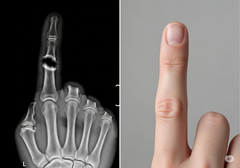

La fusion vertébrale est une procédure courante pour traiter les douleurs dorsales débilitantes en reliant deux ou plusieurs vertèbres, mais elle peut avoir un taux d'échec élevé. Les traitements actuels reposent souvent sur des greffes osseuses ou des facteurs de croissance puissants qui peuvent parfois entraîner des complications, telles qu'une formation osseuse incontrôlée en dehors de la zone ciblée.

L'approche de Bone Biologics est centrée sur la protéine NELL-1, un facteur de croissance naturellement impliqué dans le développement osseux. Des études précliniques ont montré que NELL-1 est capable de stimuler une croissance osseuse robuste précisément là où elle est nécessaire, tout en inhibant la formation de cellules adipeuses, un problème courant avec d'autres produits biologiques. Cette action ciblée pourrait conduire à des fusions plus fiables et à moins de complications.